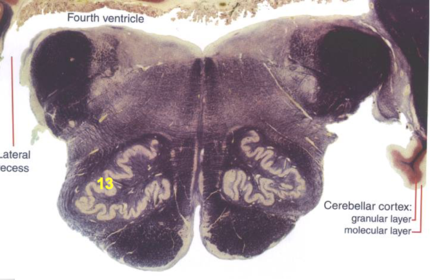

| Longitudinal pontine fibers (corticospinal tract) | |

| Transverse pontine fibers (dark fibers) | |

| Pontine nuclei (pale) | |

| Medial lemniscus | |

| ALS | |

| Trapezoid body | |

| Ventral trigeminothalamic tract | |

| Superior olive | |

| Central tegmental tract | |

| Facial nerve root fibers - descending | |

| Facial motor nucleus | |

| Interposed nuclei | |

| Medial longitudinal fasciculus | |

| Facial nerve root - internal genu | |

| Abducens nucleus | |

| Lateral vestibular nucleus | |

| Superior vestibular nucleus | |

| Inferior cerebellar peduncle | |

| Superior cerebellar peduncle | |

| Dentate nucleus | |

| Fastigial nucleus | |

| Anterior spinocerebellar tract | |

| Spinal nucleus of V | |

| Spinal tract of V | |

| Middle cerebellar peduncle | |

| Principle nucleus of V | |

| Mesencephalic V tract | |

| Trigeminal root fibers | |

| Motor nucleus of V | |

| Cerebellar vermis | |

| Lateral lemniscus | |

| Longitudinal pontine fibers (c-spinal, c-bulbar, c-pontine fibers) | |

| Transverse pontine fibers (dark) | |